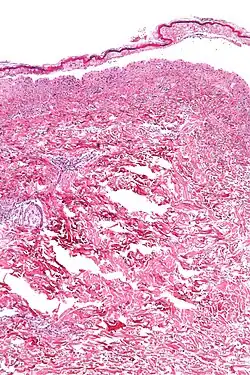

Histologisches Präparat einer Hautnekrose wie sie bei einem TEN vorkommt.

Histologisch zeigen sich beim medikamentös induzierten Lyell-Syndrom eine Spaltbildung und Abhebung der gesamten Epidermis, während sich beim staphylogen verursachten Lyell-Syndrom eine Abhebung des Stratum corneum vom Stratum granulosum zeigt.[26]

Bei der medikamentös induzierten Form zeigt sich histologisch eine subepidermale Blase mit einem oberflächlichen Infiltrat aus Lymphozyten und gelegentlich Granulozyten. Die gesamte Epidermis ist abgelöst und nekrotisch mit einem normalen korbgeflechtartigen Stratum corneum. Die Papillen der Dermis sind intakt. Vereinzelt finden sich Extravasate von Erythrozyten.[27]